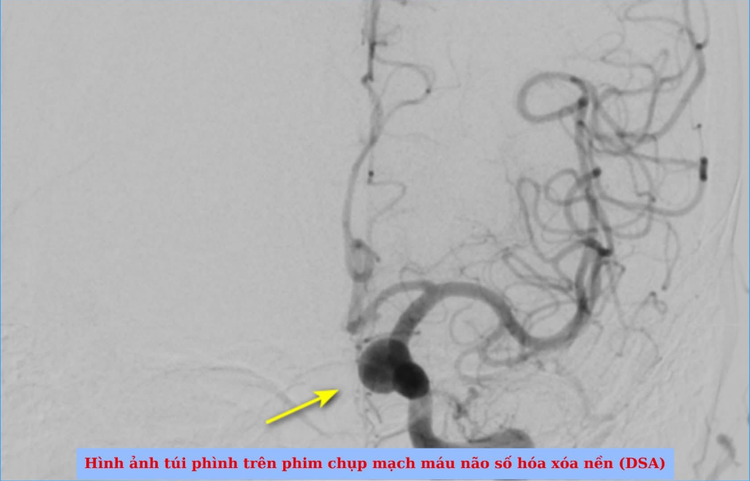

Nữ bệnh nhân tên N.T.Q, 50 tuổi, ngụ tại phường Thủ Đức, TP HCM tình cờ phát hiện túi phình động mạch cảnh trong đoạn mấu giường khi đi khám sức khỏe định kỳ. Kết quả chụp MRI 3T cho thấy túi phình có kích thước 10 x 8 mm, cổ túi phình rộng 6 mm – một trường hợp được đánh giá là có túi phình khá lớn.

stent1.png